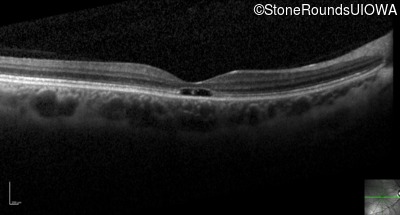

Optical Coherence Tomography - Right - 20/20 -1

Exemplar / OCT Stack